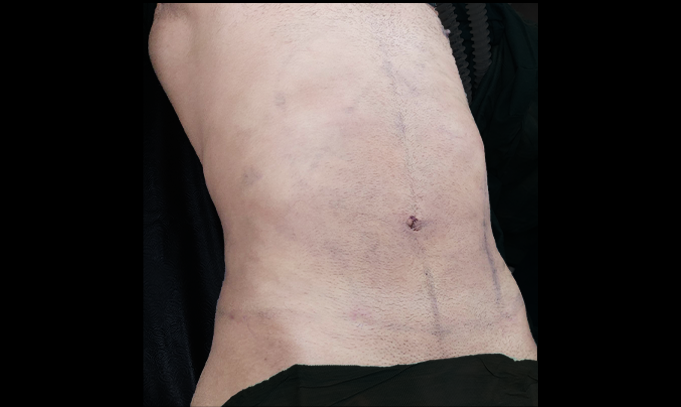

In this case, the patient presented with loose skin and muscle laxity following significant weight loss. The primary goal was to restore abdominal firmness, redefine waist contour, and improve overall body proportion — while maintaining a natural silhouette.

The procedure involved careful skin excision and muscle tightening to achieve a smoother, more structured abdominal profile.

Abdominal contouring is not only about removing excess skin — it is about rebuilding structural support and restoring harmony between the waistline and body frame.

Precision in planning and execution ensures results that look proportionate, refined, and naturally aligned with the patient’s anatomy.

The outcome focused on achieving a flatter abdomen, improved waist definition, and smoother contour transitions.

Meticulous muscle repair and conservative skin removal ensured structural support and natural body balance.